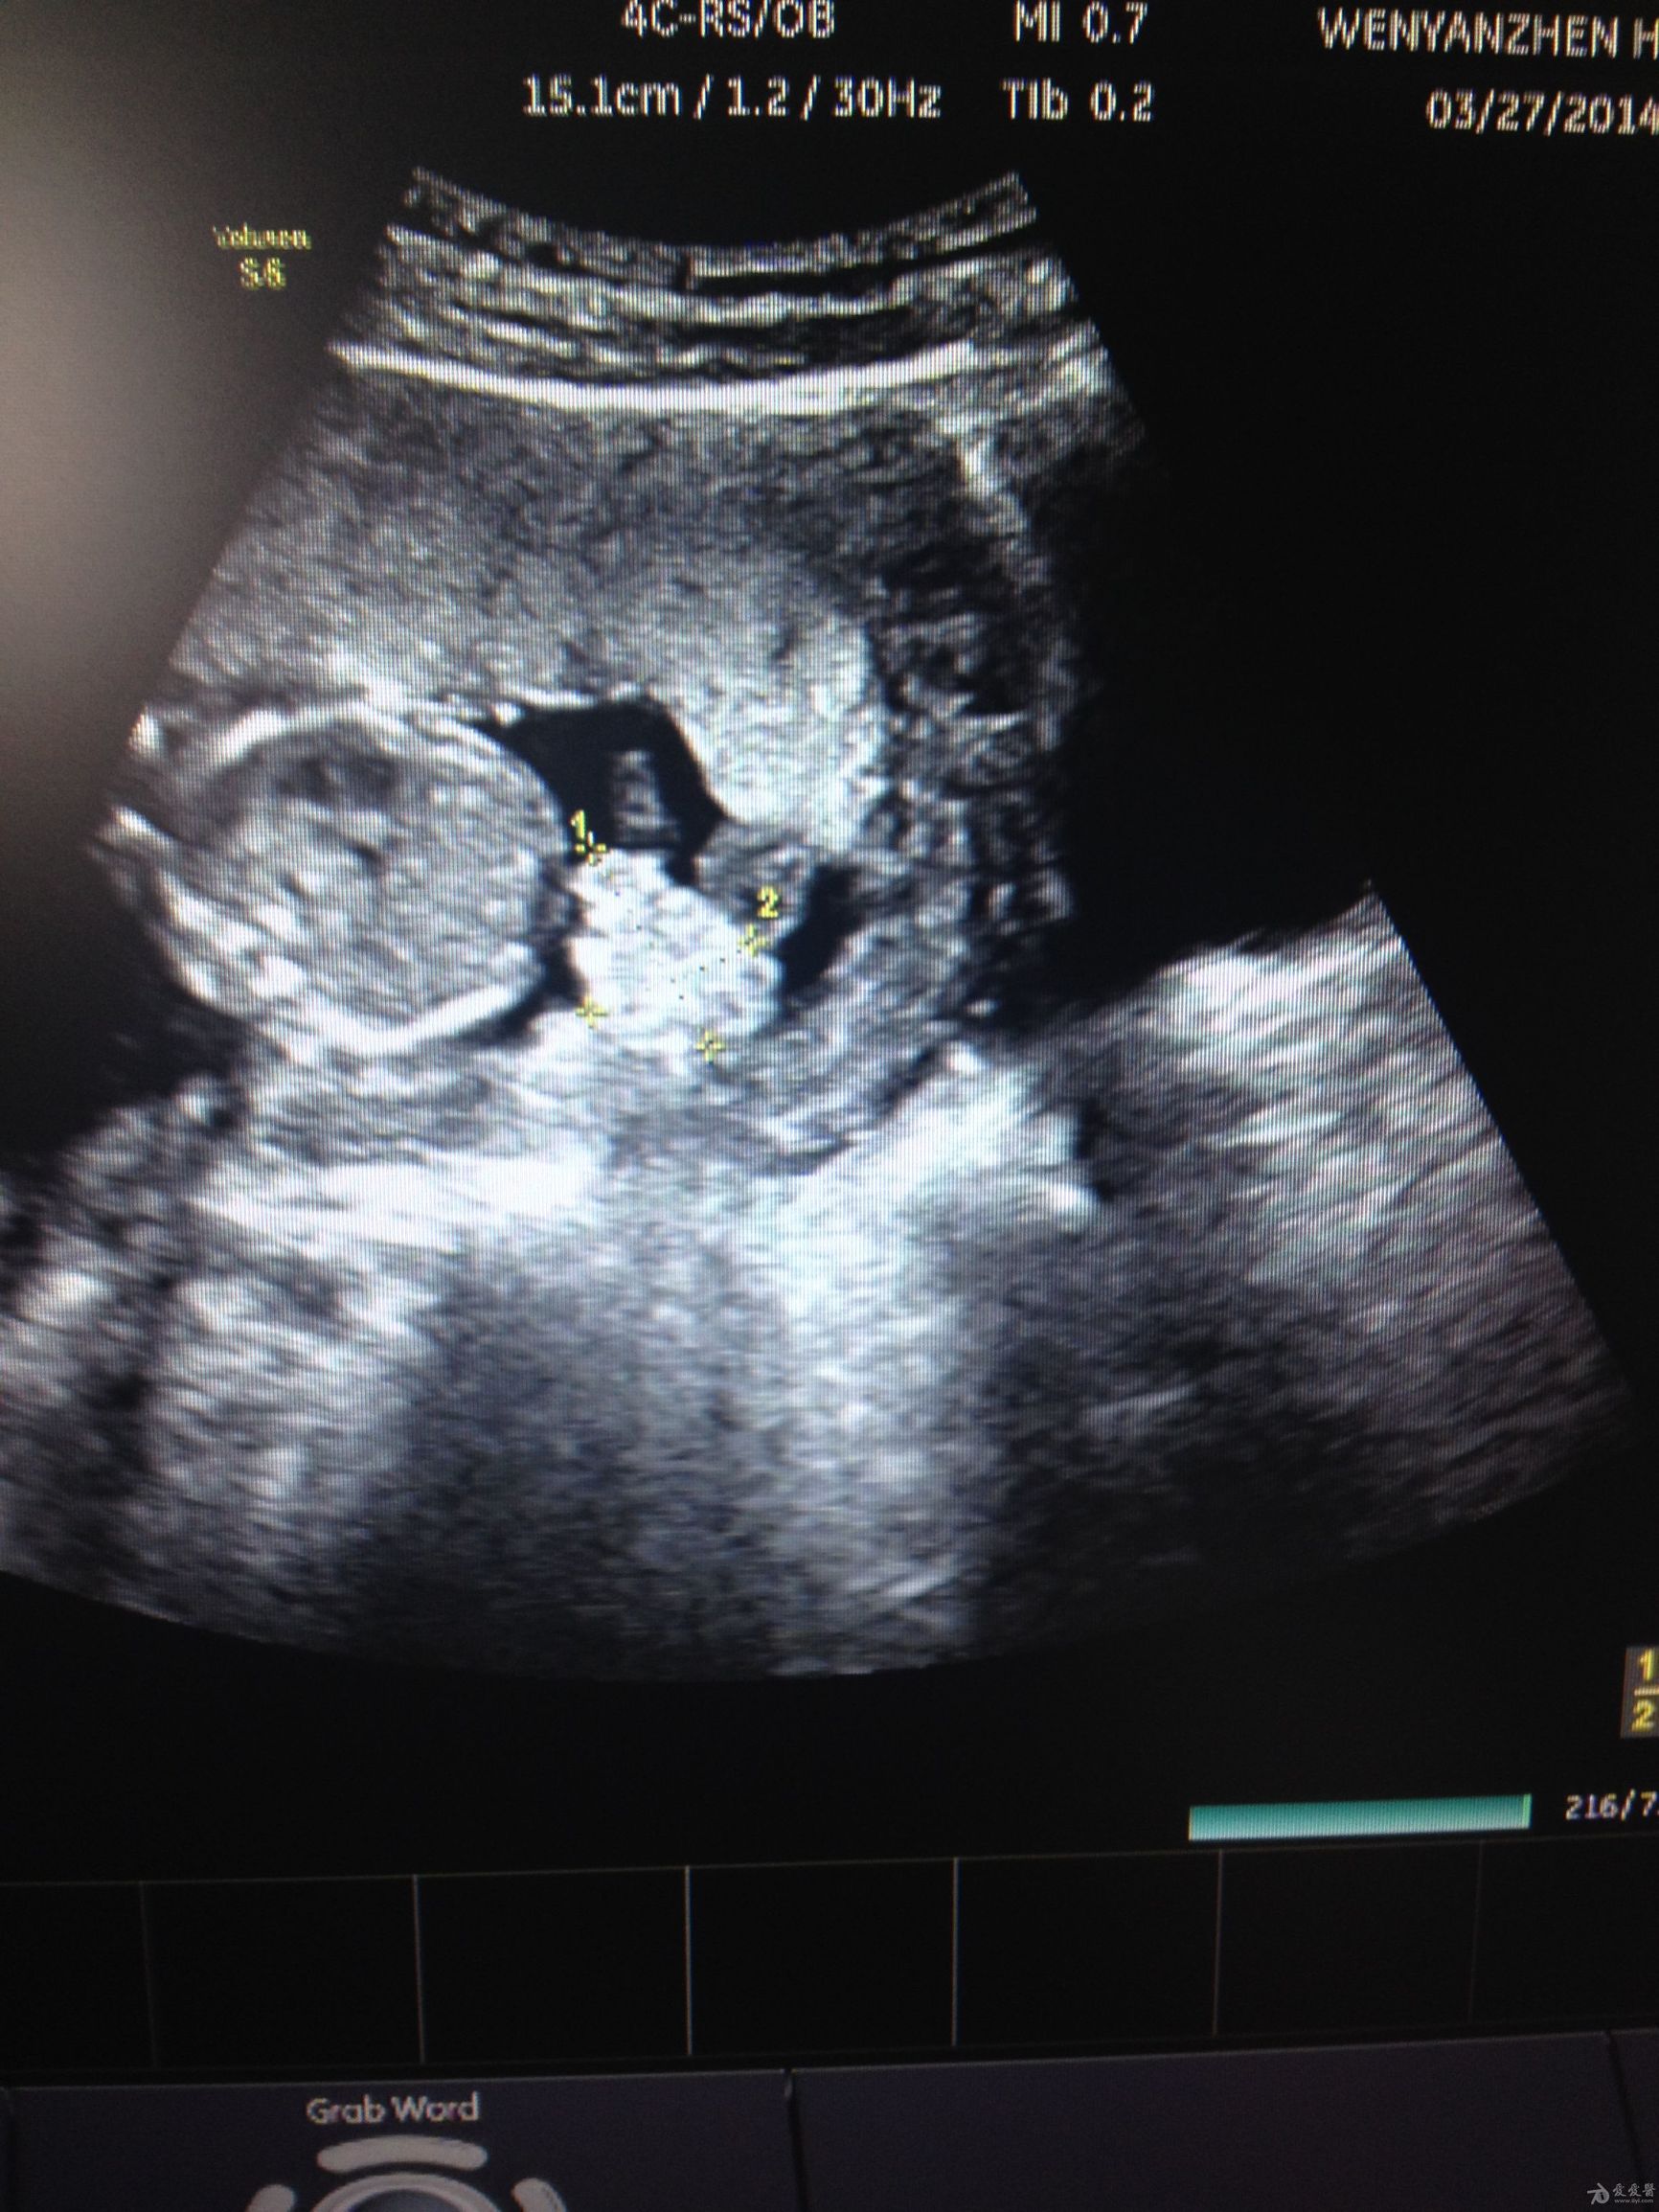

羊水深度是指,B超检查表示最大羊水池的垂直深度,小于2cm表示羊水过少,大于8cm表示羊水过多。 它为医学专业名词,是判断羊水多少的一个重要指标。羊水多,则胎儿可以健康成长;羊水少,就可以在胎儿临产期造成胎粪淤积,甚至早产或窒息。B超检查表示最大羊水池的垂直深度,羊水深度3-8cm为正常羊水量。小于3cm提示羊水过少,大于8cm提示羊水过多。

羊水指数:是将子宫分成左上,右上,左下和右下四个象限,四个象限的最大羊水暗区垂直深度之和为AFL,若AFL大于24cm诊断为羊水过多,若AFL在18-24cm之间时为可疑羊水过多或羊水偏多。

羊水测量:羊水量的测量,是评估怀孕正常与否的重要指标。但隔了一层肚皮,我们实在很难正确地去评估羊水的多少。

目前,医院大多是通过超音波来了解羊水量的状况,采取"羊水指数法"来确定羊水量是否正常。方法是:将子宫分为四个象限,分别量每个象限中羊水的最大深度,再相加求其总和。总和值在8~27厘米的范围之内属于正常状态,小于8为羊水过少,大于24则为羊水过多。